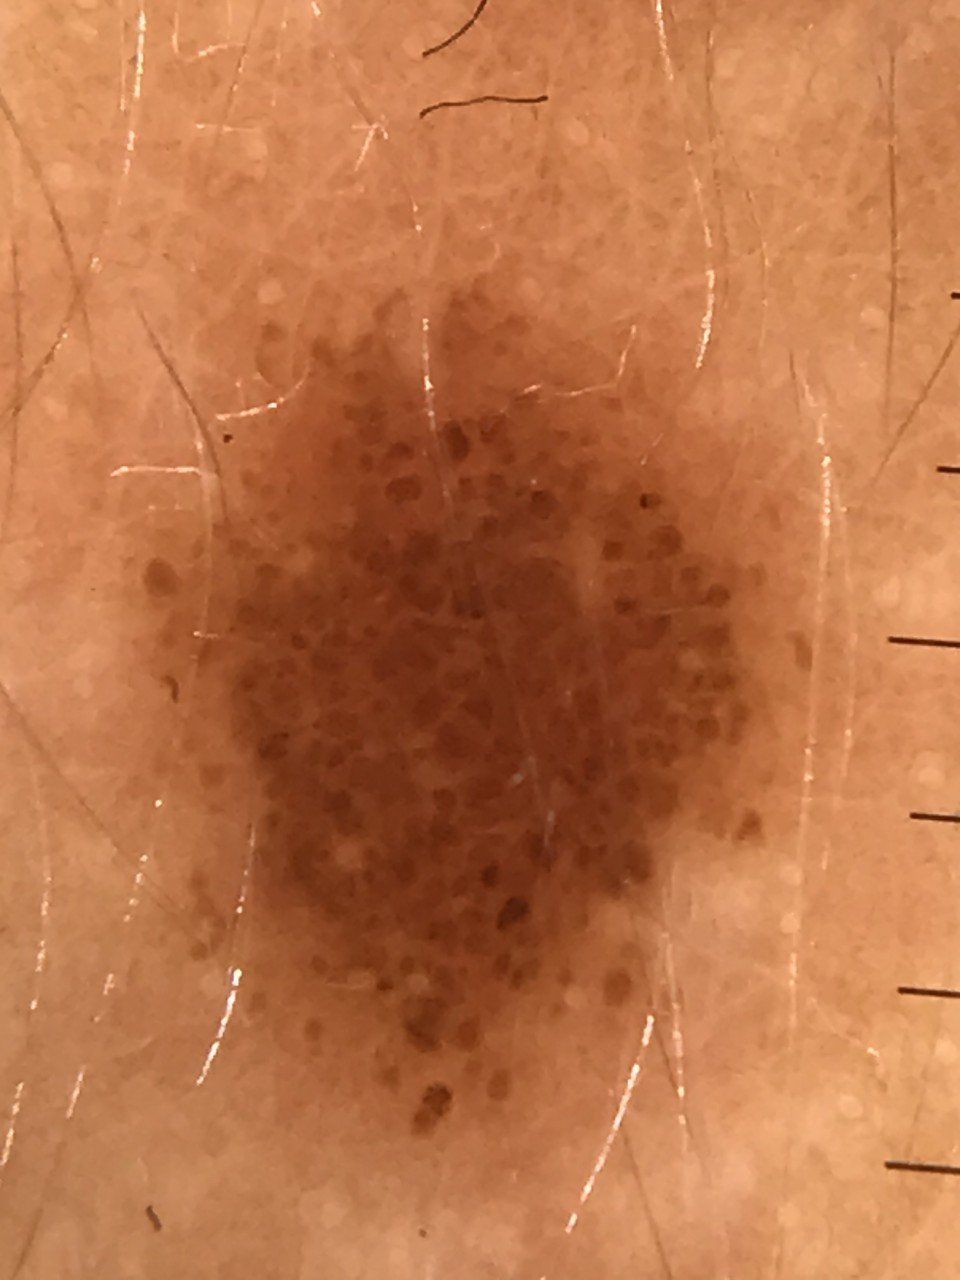

Gli studi medici del Dott. Marco Michelini, situati ad Alessandria, La Spezia e Canelli, sono dotati di un sistema digitale per l’effettuazione di una migliore diagnosi delle neoformazioni cutanee / mappatura dei nei per melanoma, la dermatoscopia.

Questa tecnica diagnostica, che non è né invasiva né dolorosa, e quindi priva di qualsiasi rischio per il paziente, può essere effettuata anche durante la gravidanza e viene impiegata soprattutto per la diagnosi precoce del melanoma.

Il sistema digitale di mappatura dei nei per melanoma, e la possibilità di archiviare su computer e conservare i dati, permette di documentare anche nel tempo le evoluzioni delle caratteristiche dermatoscopiche, sia pigmentate che non dei nei. Se vengono riscontrate delle anomalie e delle irregolarità strutturali, è quindi possibile tracciare il percorso delle possibili variazioni morfologiche durante gli eventuali controlli successivi. In questo modo, il medico e il paziente possono avere sott’occhio sempre un quadro completo della situazione, e decidere di conseguenza il da farsi in tutta serenità.